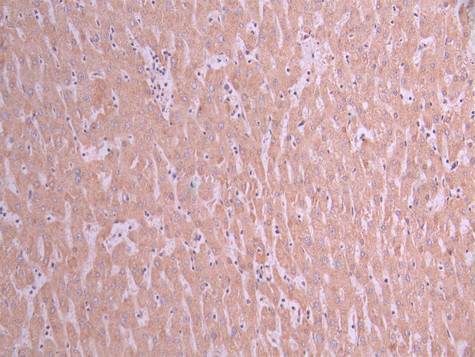

• IHC image of CSB-RA083975A0HU diluted at 1:100 and staining in paraffin-embedded human liver cancer performed on a Leica BondTM system. After dewaxing and hydration, antigen retrieval was mediated by high pressure in a citrate buffer (pH 6.0). Section was blocked with 10% normal goat serum 30min at RT. Then primary antibody (1% BSA) was incubated at 4°C overnight. The primary is detected by a Goat anti-rabbit polymer IgG labeled by HRP and visualized using 0.05% DAB.